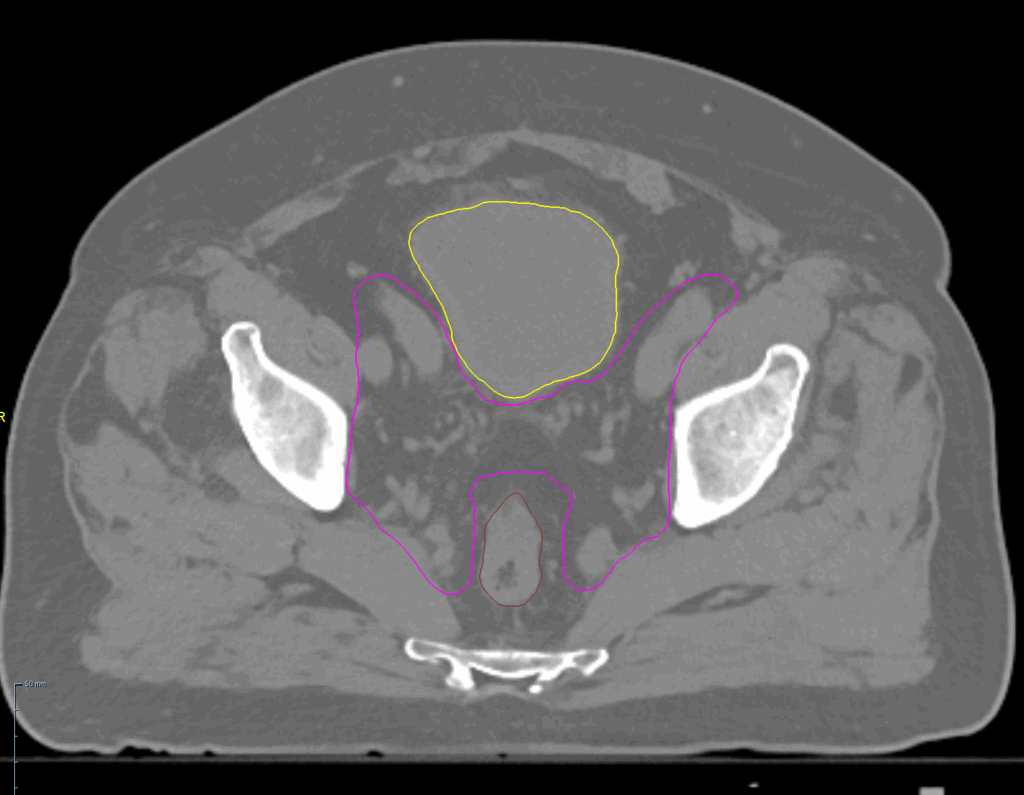

Prostate Bed

< View All Plan Studies RADIXACT SYSTEM Prostate Bed Case History AGE: 76-year-oldGENDER: Male Medical History Immidiate tolerance: Grade II dermatitis with eyelid edema, Grade I conjunctivitis resolved with Sterdex Diagnosis: Squamous cell carcinoma of the right lower eyelid Planning CT Images Treatment Plan Images ClearRT® Images Treatment Planning Highlights Fractionation / Protocol Used66 Gy […]